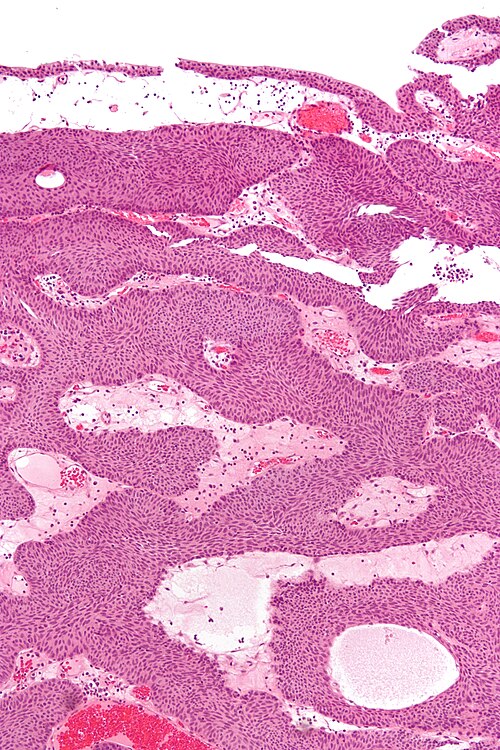

English: High magnification micrograph of an inverted papilloma. H&E stain.

This entity may be confused with an invasive urothelial carcinoma; features that differentiate these entities and suggest malignancy are the presence of:

1. Mitoses.

2. Atypical mitosis.

3. Nuclear atypia (variable nuclear size, shape and staining).

4. Stromal invasion/desmoplastic stroma.